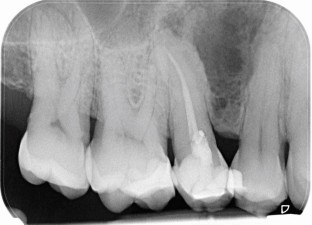

Chhabra, H., Killick, Z. & Bailey, E. Botryoid cyst. Br Dent J 233, 859 (2022). https://doi.org/10.1038/s41415-022-5265-8